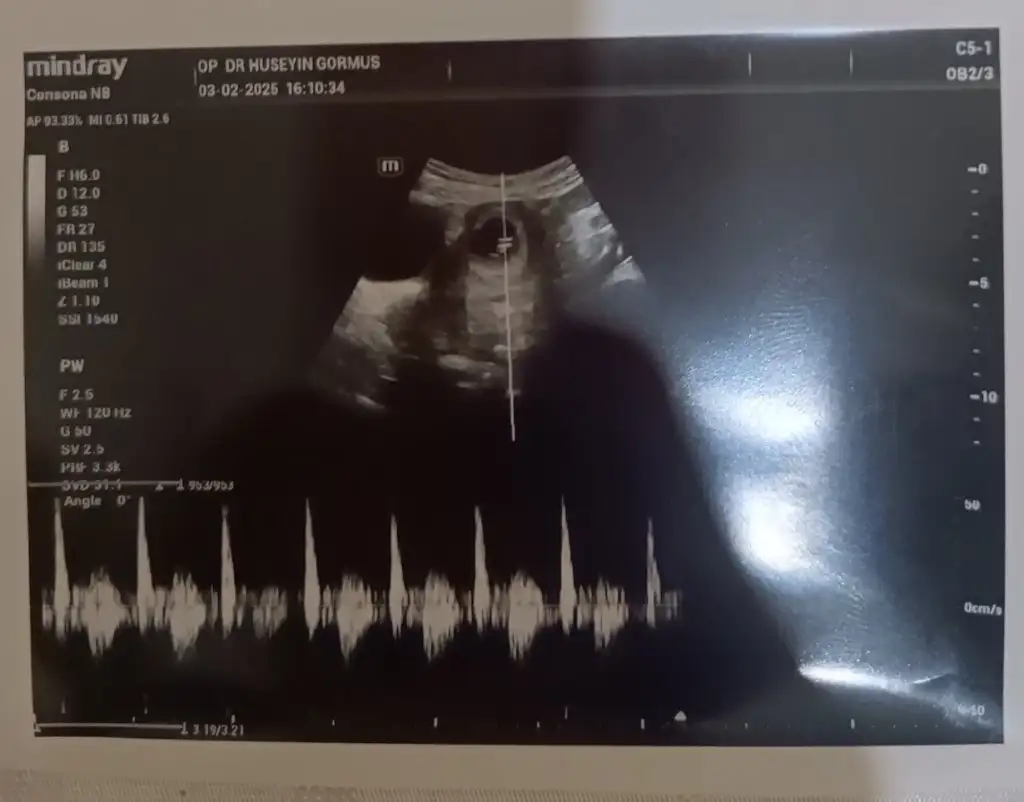

Kizlar bende az çok ramziden anlıyorum ama bu ultrason farklı geldi ultrason terimleri sol tarafta kalınca bebekte sagdamidir soldamidir çözemedim anlayan varsa cinsiyet tahmininde bulunabilirmi M meryem2132 Rica etsem sende bakarmisin kafam karıştı da benim